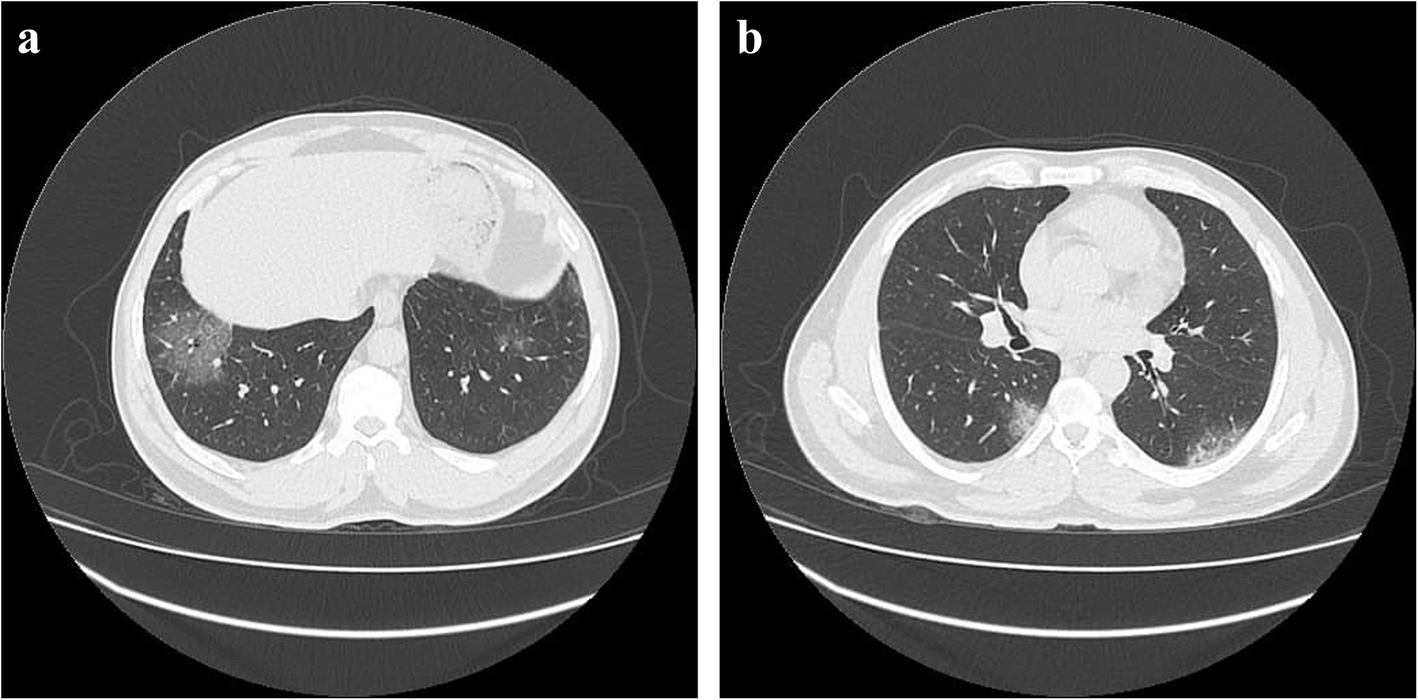

a Male, 14 years old. Chest CT showed bilateral basal ground glass opacities. b Male, 15 years old. Chest CT showed crazy paving pattern in both lungs